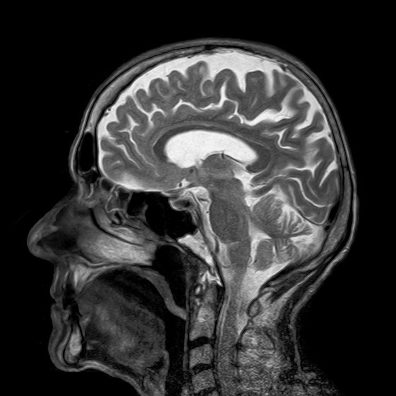

Dy eksperimente të implanteve në tru tregojnë përparim të rëndësishëm në këtë fushë, sipas një artikulli të botuar të mërkurën në revistën Nature.

Pat Bennett, 68 vjeç, ishte një atlete derisa u diagnostikua me sëmundjen e Charcot më shumë se një dekadë më parë. Kjo sëmundje neurodegjenerative, e cila në mënyrë progresive e privon pacientin nga të gjitha lëvizjet deri në paralizë të plotë, fillimisht u reflektua tek ajo nga vështirësitë në të folur, pastaj nga pamundësia për të folur, shkruan RTS.

Studiuesit nga Departamenti i Neurokirurgjisë në Universitetin Amerikan të Stanfordit implantuan katër katrorë të vegjël prej 64 mikroelektrodash të bëra prej silikoni në mars 2022. Duke depërtuar në korteksin cerebral për vetëm 1.5 milimetra, ata regjistrojnë sinjalet elektrike të prodhuara nga zonat e trurit të lidhura me prodhimin e gjuhës.

Sinjalet e prodhuara përcillen jashtë kafkës përmes një tufe kabllosh dhe përpunohen nga një algoritëm. Makina “mësoi”, gjatë katër muajve, të interpretonte kuptimin e saj. Ai lidh sinjalet me fonemat – tingujt që formojnë fjalët e një gjuhe – dhe i përpunon ato me ndihmën e një modeli gjuhësor, përcjell albinfo.ch.

Me ndërfaqen e tij tru-makinë (BMI), Pat Bennett flet përmes një ekrani me shpejtësinë prej më shumë se 60 fjalë në minutë. Ende larg 150 deri në 200 fjalë në minutë të një bisede standarde, por tashmë tri herë më shpejt se në rekordin e mëparshëm, që daton nga viti 2021 dhe tashmë i mbajtur nga ekipi që e mori nën krahun e tij. Shkalla e gabimit në një fjalor me 50 fjalë ka rënë në më pak se 10%, nga më shumë se 20% më parë, shkruan RTS.

Në eksperimentin e dytë, të kryer nga ekipi i Edward Chang në Universitetin e Kalifornisë, pajisja mbështetet në një rrip elektrodash të vendosura në material kortikal. Performanca e tij është e krahasueshme me sistemin e ekipit të Stanfordit, me një mesatare prej 78 fjalësh në minutë, pesë herë më shpejt se më parë.